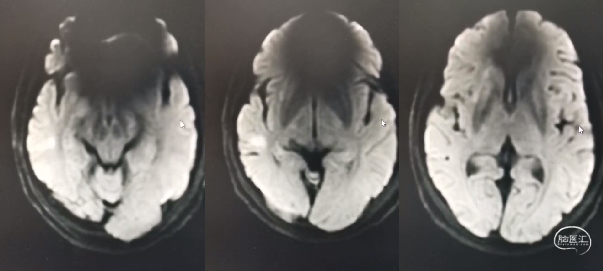

术前影像学检查

MRI平扫未见新鲜梗死:

高分辨 MRI:

DSA: